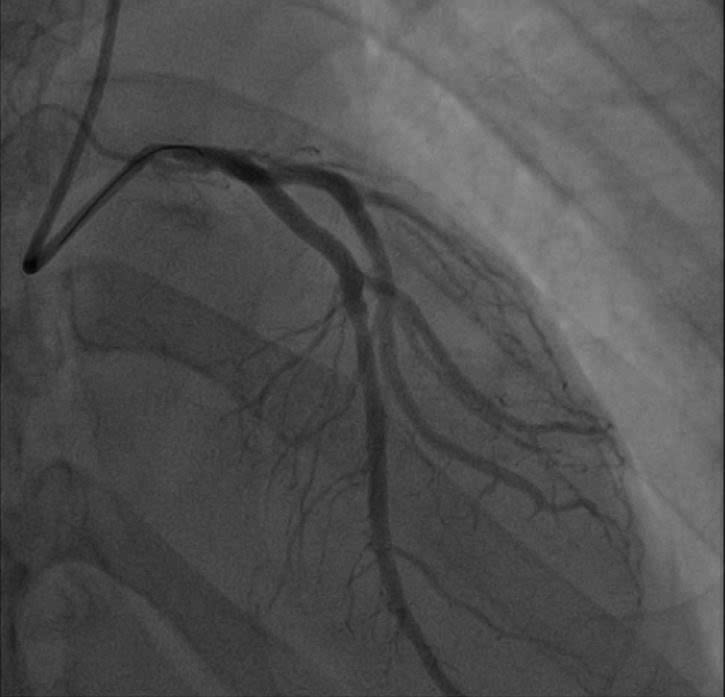

Cuộc chạy đua với thời gian: Khi y học hiện đại "hồi sinh" trái tim

Các bác sĩ Bệnh viện E vừa cấp cứu vừa hồi sức và khẩn trương thực hiện các thăm dò cận lâm sàng tìm nguyên nhân cho người bệnh. Kết quả chụp động mạch vành đã hé lộ nguyên nhân thực sự: Động mạch liên thất trước (LAD) – nhánh động mạch quan trọng nhất nuôi tim – đã bị tắc nghẽn tới 99%. Đây là hậu quả của tình trạng xơ vữa lan tỏa, dù trước đó anh M. chỉ có biểu hiện đau thắt ngực nhẹ mà anh lầm tưởng là trào ngược dạ dày.

Các bác sĩ thực hiện can thiệp mạch vành qua da (PCI) cho người bệnh. Kết quả chụp mạch số hóa xóa nền (DSA) xác định tổn thương hẹp khít 99% đoạn gần nhánh liên thất trước (LAD) – vốn được mệnh danh là "động mạch của sự sống". Các bác sĩ tim mạch can thiệp đã nhanh chóng triển khai kỹ thuật đặt Stent, giải phóng điểm tắc nghẽn, tái lập dòng chảy mạch vành để cứu vãn vùng cơ tim đang thiếu máu cục bộ cấp tính và ngăn chặn các cơn loạn nhịp nguy hiểm.

Tim bị hẹp tắc được can thiệp thành công - Ảnh BVCC